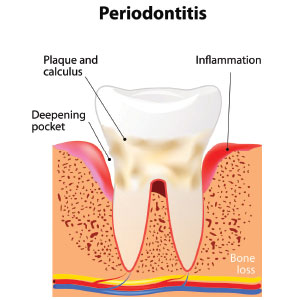

When gum disease is left untreated or has advanced to periodontitis, you may require periodontal treatment to restore you back to oral health.

Gum disease which remains untreated can cause problems with the jawbone which could ultimately lead to the loss of your natural teeth. As plaque builds up on the gum line, it makes the area more vulnerable to bacteria and infection. In recent years, many links have been made between gum disease and general health, so it is a problem that should not be ignored. It is important to stay on top of your dental health through regular visits to your dentist and the hygienist so your teeth and gums can be cleaned thoroughly

In the first instance, you will be treated at the practice by either the dentist or hygienist, however, if you have advanced periodontitis and need the attention of a specialist you may require a surgical procedure. We will help you to understand any treatments that may be required.